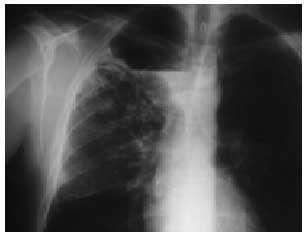

En el control radiográfico posterior se aprecia la aparición de un nivel hidroaéreo dentro de la bulla del enfisema, así como la desaparición del infiltrado alveolar (figs. 2 y 3). Se realizó también una fibrobroncoscopia, con resultado normal, y en la TC se aprecia una imagen compatible con una bulla infectada en el lóbulo superior derecho. Tras completar el tratamiento antibiótico y realizar pruebas de función respiratoria, el enfermo está a la espera de ser sometido a intervención por el servicio de cirugía torácica.

Fig. 2. Radiografía de tórax donde se aprecia el inicio del nivel hidroaéreo y la mejoría del infiltrado neumónico.

Fig. 3. Radiografía de tórax con resolución del infiltrado pulmonar y nivel hidroaéreo claramente definido en la bulla.